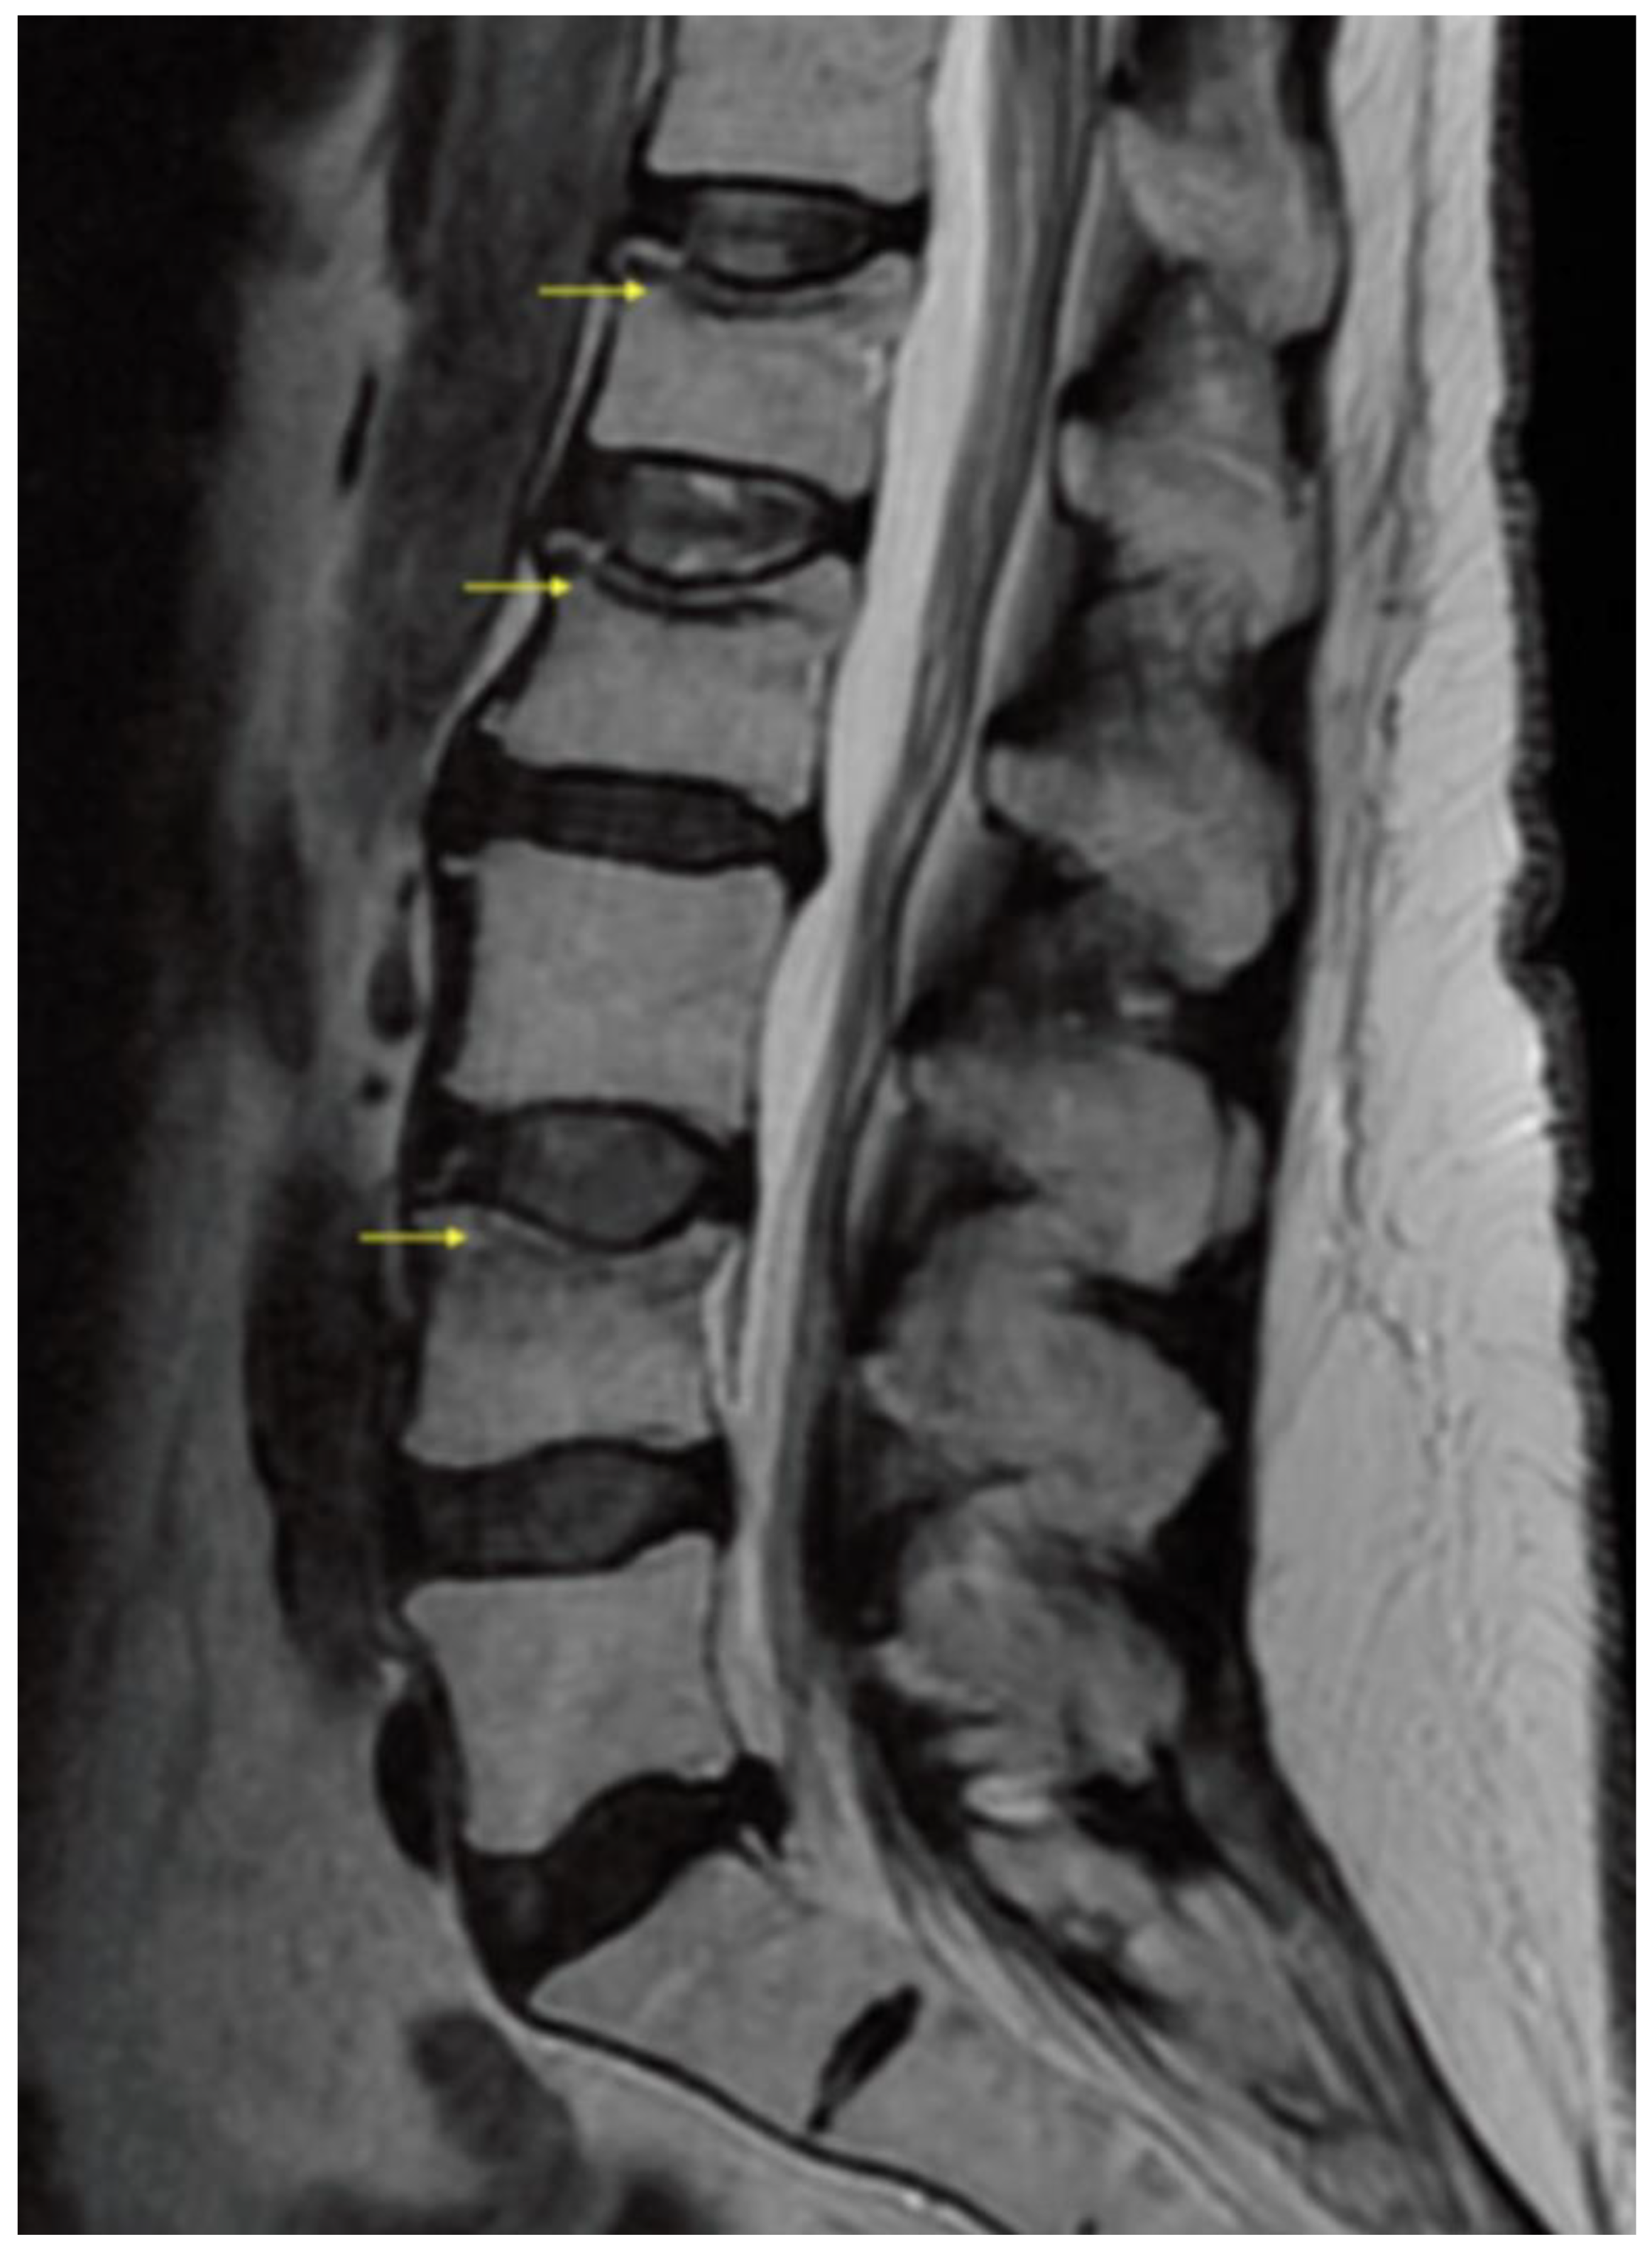

3. Results/Case Report